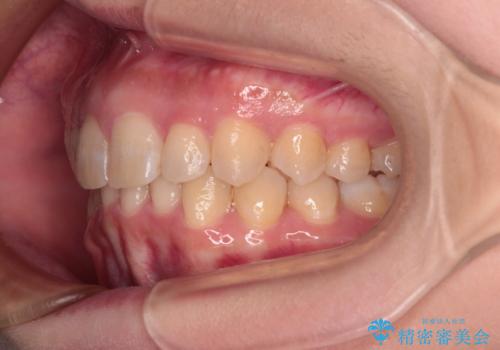

- 上の前歯の出っ歯と前歯の深い咬み合わせを治したいとのことで来院された患者様です。

上顎の歯は後方移動とIPR(歯と歯の間を削る)によって口元が引っ込むように、下顎は歯列全体の拡大とIPRによって上顎とバランスよく咬み合うように設計し、インビザラインにより治療を行うこととしました。

上顎歯列の後方への移動量が多く、右側の奥歯の咬み合わせを改善する必要もあったため、治療には長期間を要しました。